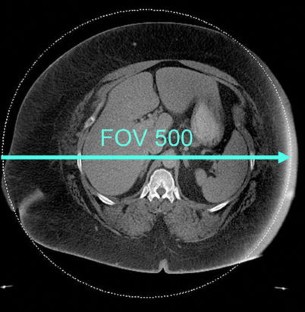

Fig. 3